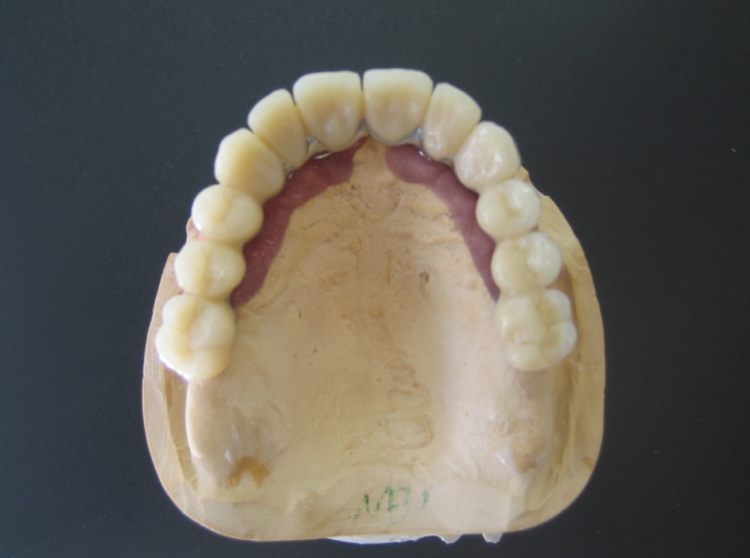

Implants have established themselves as the most durabledental prosthesis - they help not only to create a beautiful smile and aesthetics but also to improve the quality of life. An implant takes the function of a tooth root and forms the pillar for the dentures. It is invisible in the jaw and firmly anchored. For the implants only pure titan material is used, since this material has a high body tolerance and no allergies are known. One of the greatest advantages is that the healthy teeth don't need to be grinded down to fix a bridge or a removable prosthesis. With implants the patient doesn't feel any difference to his natural teeth.

Dental implants are as close to the original condition as no other restoration. The new tooth roots inteosseograte after implantation. The implanted screw serves as the foundation for single tooth crowns or bridges. Prostheses can also be securely fixed using implants. They do not have any restrictions in everyday life, such as laughing, talking or chewing.